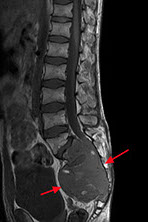

Aneurysmal bone cyst (ABC)

- usually an impressive, "benign" expansile lesion that destroys bone; etiology unknown, prolly a rxn to interosseous hemorrhage

- seen in pts <20 yo, presenting c pain, swelling, MC in metaphysis

-- can compress nerve root if goes vertebral and grow very fast

Imaging: MC in metaphysis of long bones or posterior aspect of vertebra, "soap bubble" characteristic

- CT shows thin rim of sclerosis at margins, and can have fluid-fluid levels (double meniscus 2/2 old blood c lighter overlying watery fluid, or can have soap-bublle appearance

Micro: if intact, see cavernous blood-filled spaces lined by fibrous septae

- septae made of loose / edematous tissue c spindle cells, giant cells, capillaries and thin strands of osteoid or bone + mixed inflam

- can have lots o mits, but not that much atypia